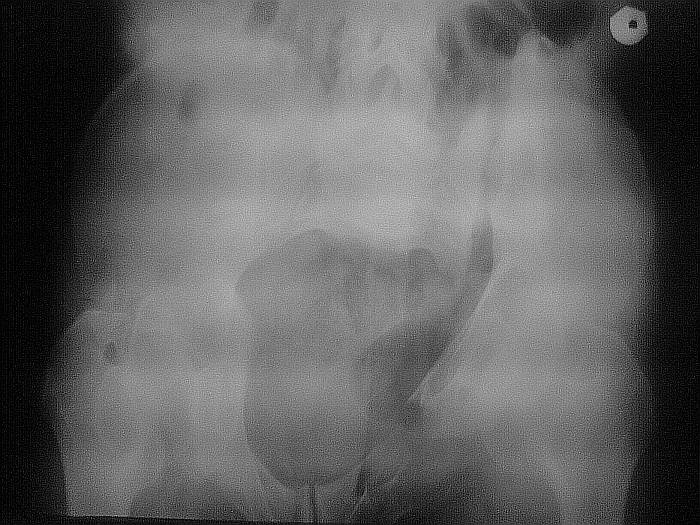

Вложение не в текстовом формате было извлечено…

Имя     : Inlet.jpg

Тип     : image/jpeg

Размер  : 76579 байтов

Описание: отсутствует

Url     : http://weborto.net:8080/pipermail/ortho/attachments/20070616/f45c096c/attachment-0004.jpg